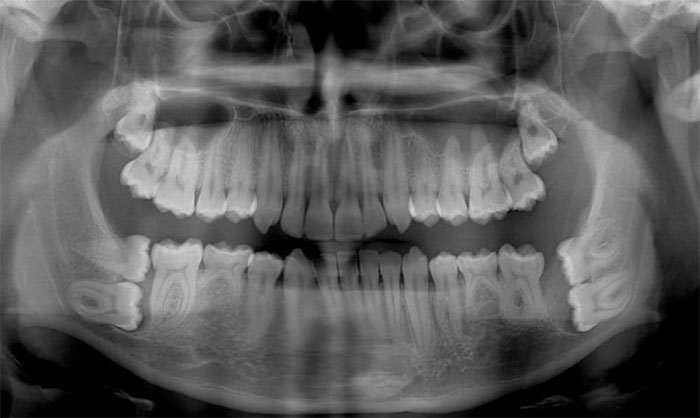

Панорамный рентген зубов. Кто-то забыл снять очки